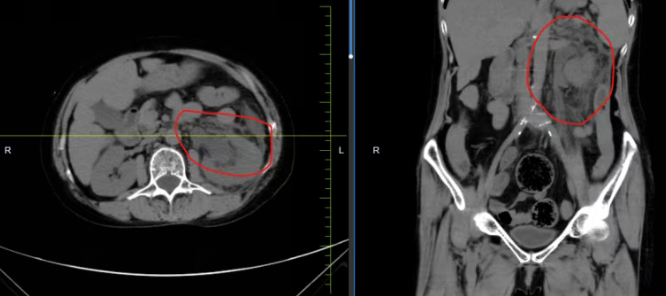

近期,长春国文医院泌尿外科成功救治一例因左侧输尿管结石合并重复肾畸形,继发严重尿源性脓毒血症、感染性休克的危重患者。科室团队严格遵循尿源性脓毒血症治疗规范,使患者转危为安,为复杂泌尿系感染危重症患者赢得了宝贵的生命转机。

该患者因左侧重复肾畸形合并输尿管上段结石,造成尿路梗阻、肾盂积水,细菌逆行感染引发急性肾盂肾炎、肾周围炎,最终诱发脓毒血症。同时患者合并高血压病3级、低蛋白血症等多种基础疾病,治疗难度显著增加。